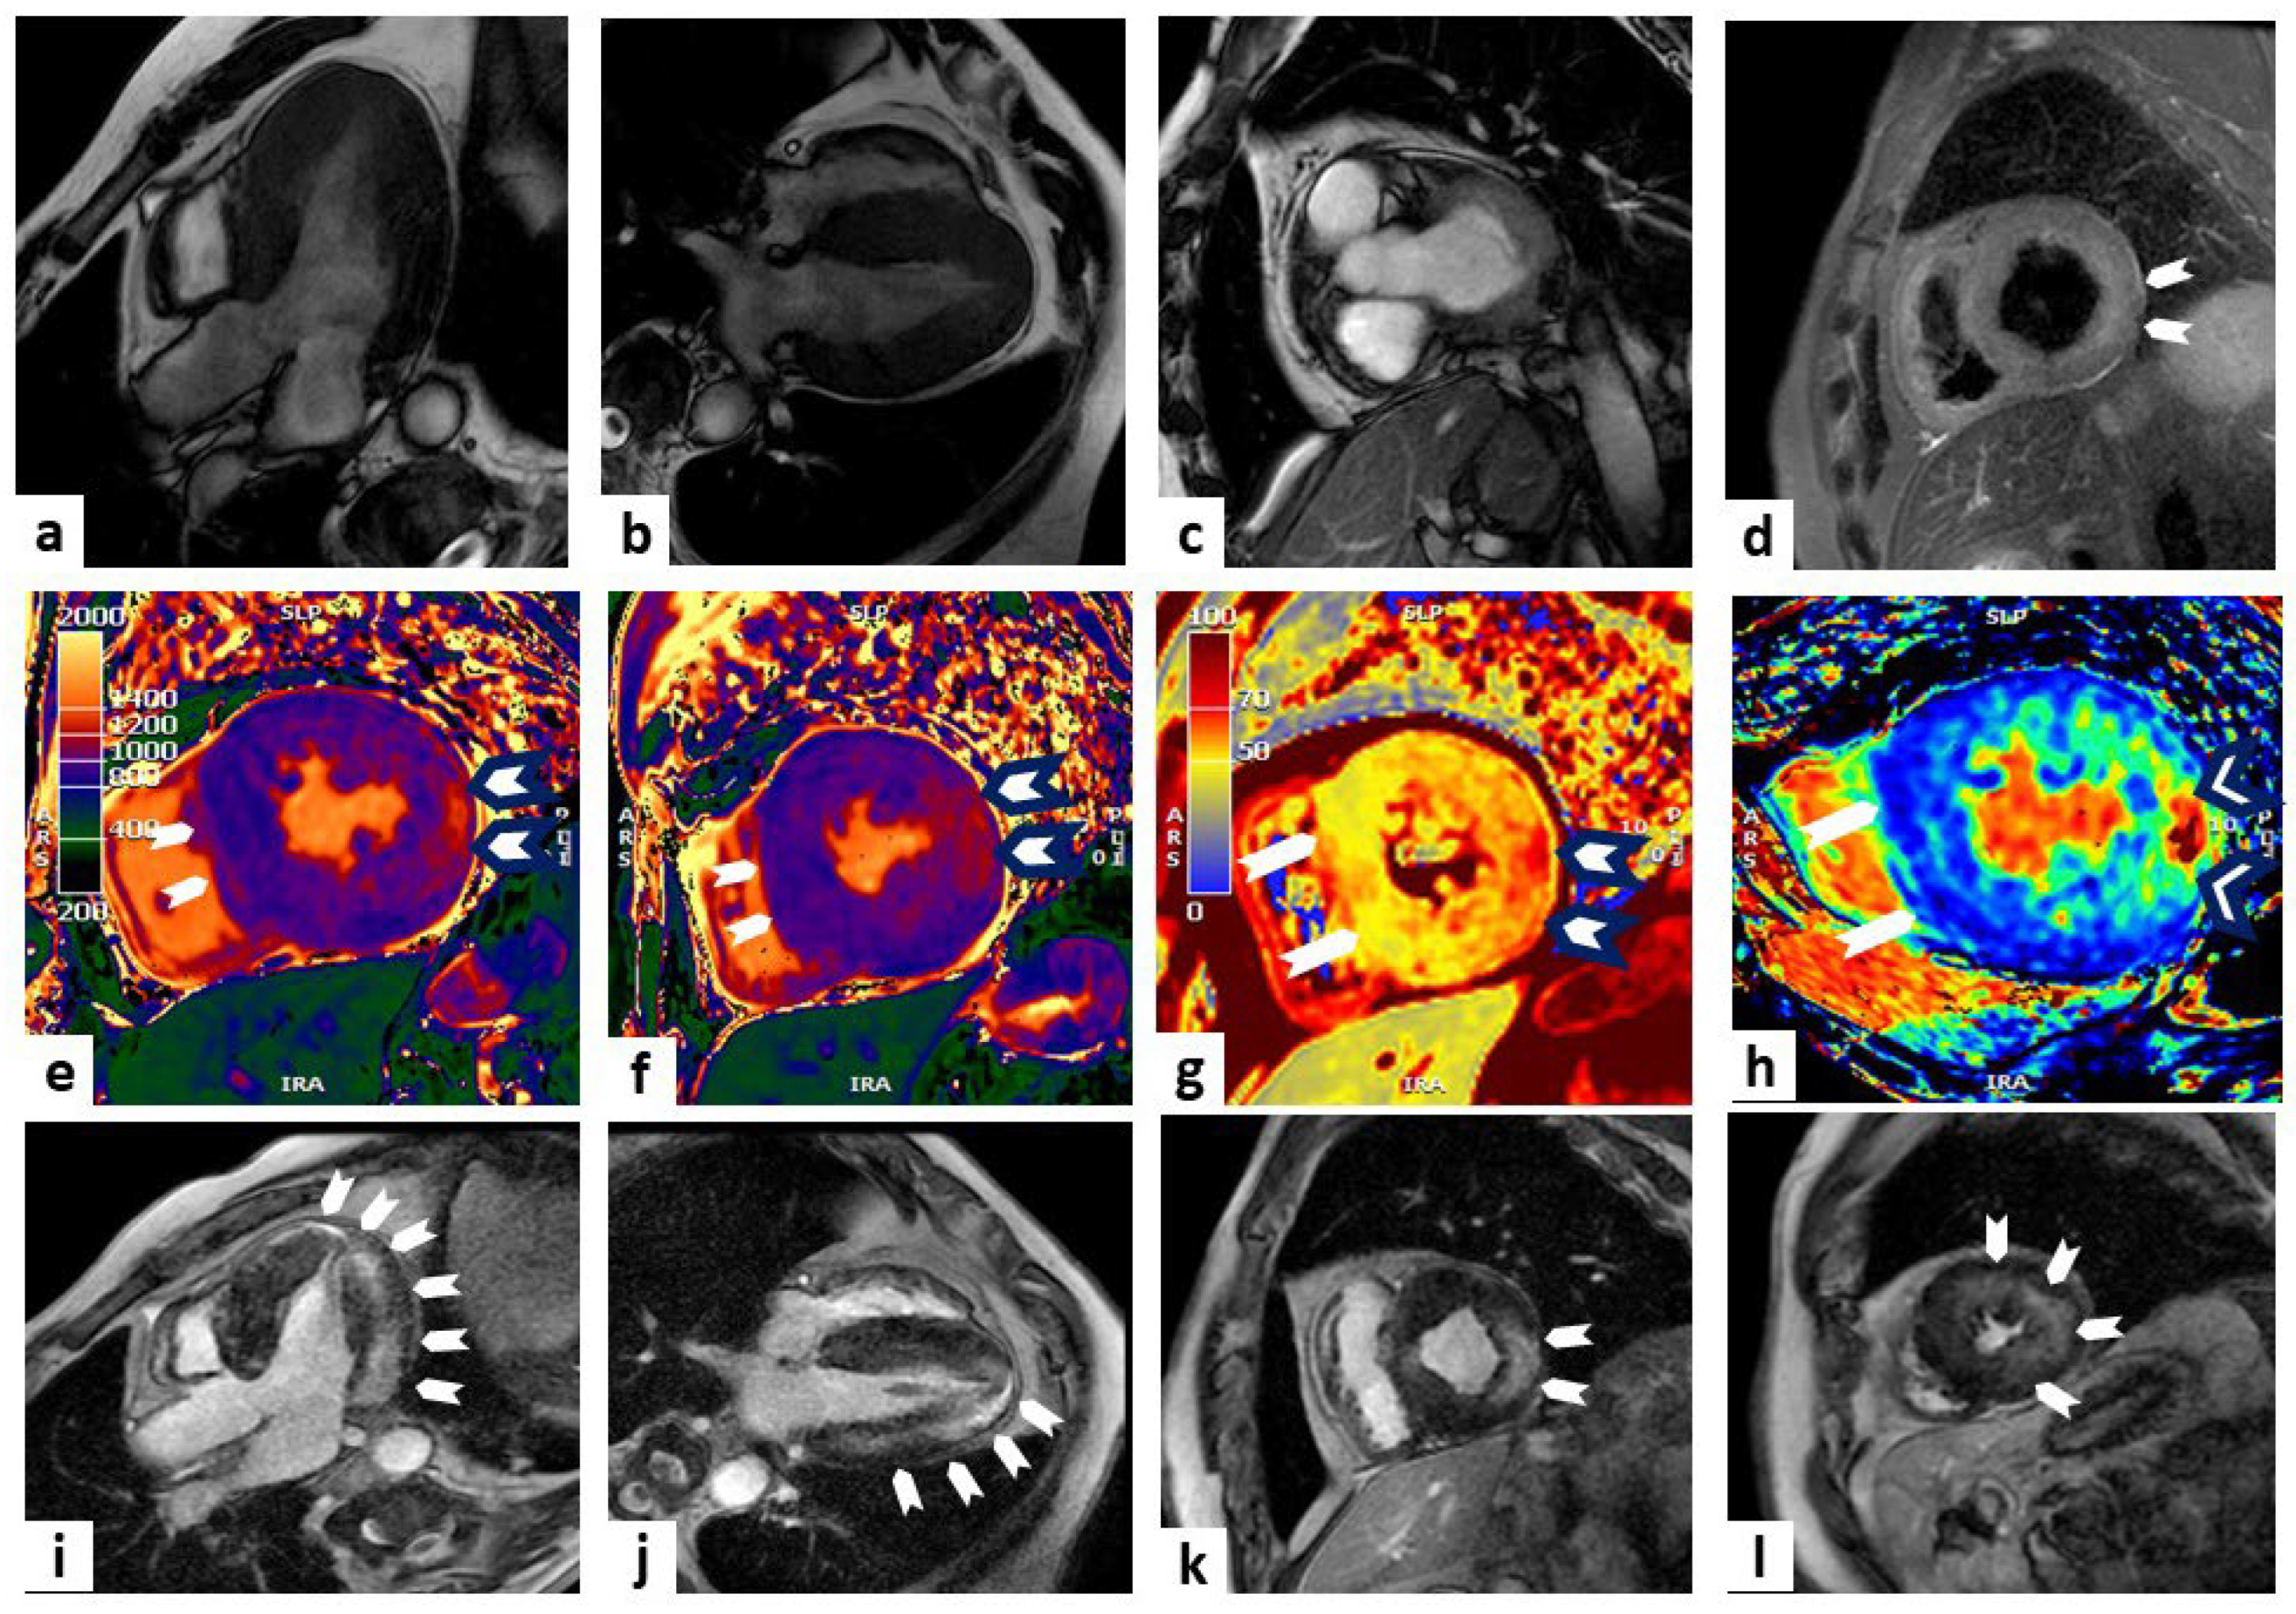

CMR represents the predominant non-invasive imaging modality in the early diagnosis and staging of AFD, as it combines the assessment of cardiac involvement and the characterization of tissue abnormalities [61] (Figure 3).

Figure 3.

Anderson–Fabry disease. One case involves a 67-year-old man who was diagnosed with Anderson–Fabry disease through genetic testing during family screening (because of his affected brother). He remains completely asymptomatic. Cardiac magnetic resonance (CMR) imaging showed concentric LV hypertrophy with a mild reduction in ejection fraction (EF) in steady-state free precession (SSFP) sequences (panels (a–c) show three-chamber, four-chamber, and short-axis views at the basal level, respectively). Panel (d) shows oedema (white arrowheads) at the level of the mid-LV short-axis view (T2-weighted sequence). Panels (e,f) display T1 mapping sequences with a low value in the septum (white arrowheads) and higher values in the lateral wall (white arrowheads with black outlines) at the level of LV papillary muscles and the mid-LV short-axis view, respectively. Panels (g,h) display T2 mapping and extracellular volume (ECV) sequences, respectively, with low values in the septum (white arrowheads) and higher values in the postero-lateral wall (white arrowheads with black outlines) at the level of the mid-LV short-axis view. Late gadolinium enhancement (LGE) sequences display a non-ischemic hyperenhancement pattern (white arrowheads) at the level of the lateral wall (panels (i–l) show three-chamber, four-chamber, mid-LV short-axis, and apical LV views, respectively).

The most common morphological finding is a concentric hypertrophy of LV and of papillary muscles, usually associated with hypertrophy of RV [62,63]. Another typical finding is the presence of LGE, described as myocardial fibrosis areas, in the basal inferolateral mid-wall of the LV with sub-endocardial sparing, found in up to 50% of subjects [58].

Intracellular accumulation of glycosphingolipids causes a reduction in nT1, especially at the basal septum, even at the early stage, that often precedes ventricular hypertrophy and may therefore be useful as a marker for early initiation of enzyme replacement therapy [64]. This makes this method useful for the early identification of cardiac involvement, before the morphological and functional alterations typical of the full-blown phases of the disease [65].

However, it has been shown that, at a more advanced stage of the disease, when inflammation is active and there is a recall of lymphocytes, there is a pseudo-normalization of T1 time that could mislead the clinician [66]. This phenomenon has led experts to propose a three-phase model of AFD: in the initial phase, termed accumulation, there is a reduction in T1 mapping; in the second phase, termed inflammatory, ventricular hypertrophy begins to manifest and T1 mapping can be within a normal range; finally, there is the irreversible terminal phase, with the development of fibrosis and evidence of LGE [66,67].